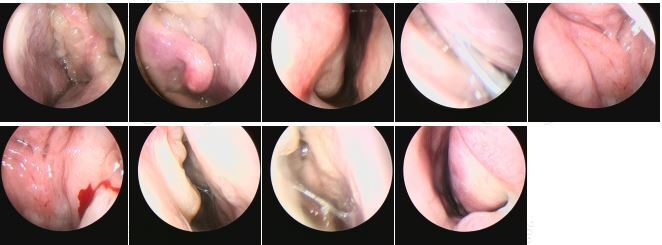

一例復(fù)發(fā)性全組鼻竇炎伴鼻息肉的患者

10年前在外院接受了全麻鼻竇炎手術(shù),術(shù)后癥狀短暫緩解,2年后再次復(fù)發(fā)。于我院就診時有明顯鼻堵、黃涕、嗅覺下降,并伴有間斷頭部悶脹感,自覺頭暈。術(shù)前CT發(fā)現(xiàn)除雙側(cè)嚴(yán)重全組鼻竇炎外,還伴有雙側(cè)眶內(nèi)壁的廣泛缺損,可能與既往外傷史或手術(shù)史有關(guān)。同時發(fā)現(xiàn)右側(cè)額篩區(qū)域黏液囊腫形成,同樣可能與既往手術(shù)時此區(qū)域開放不完全有關(guān)。此次手術(shù)我們采取鼻內(nèi)鏡下根治性手術(shù)(鼻竇輪廓化)+Draf3型額竇手術(shù)的術(shù)式,旨在充分開放所有鼻竇氣房,去除不可逆病變,尤其是可能導(dǎo)致疾病反復(fù)發(fā)作、發(fā)展的病骨,術(shù)中需要特別注意辨識并保護(hù)雙側(cè)眶內(nèi)壁骨質(zhì)缺損的位置,最終術(shù)中我們將雙側(cè)眶疝出的部分進(jìn)行了充分的輪廓化,并去除了其上方的眶上氣房、篩前動脈骨管周圍的病變。圍手術(shù)期除常規(guī)抗感染、促排、沖洗等用藥外,增加口服激素的序貫治療?;颊咝g(shù)后恢復(fù)良好,于術(shù)后第3天出院,無相關(guān)并發(fā)癥出現(xiàn)。